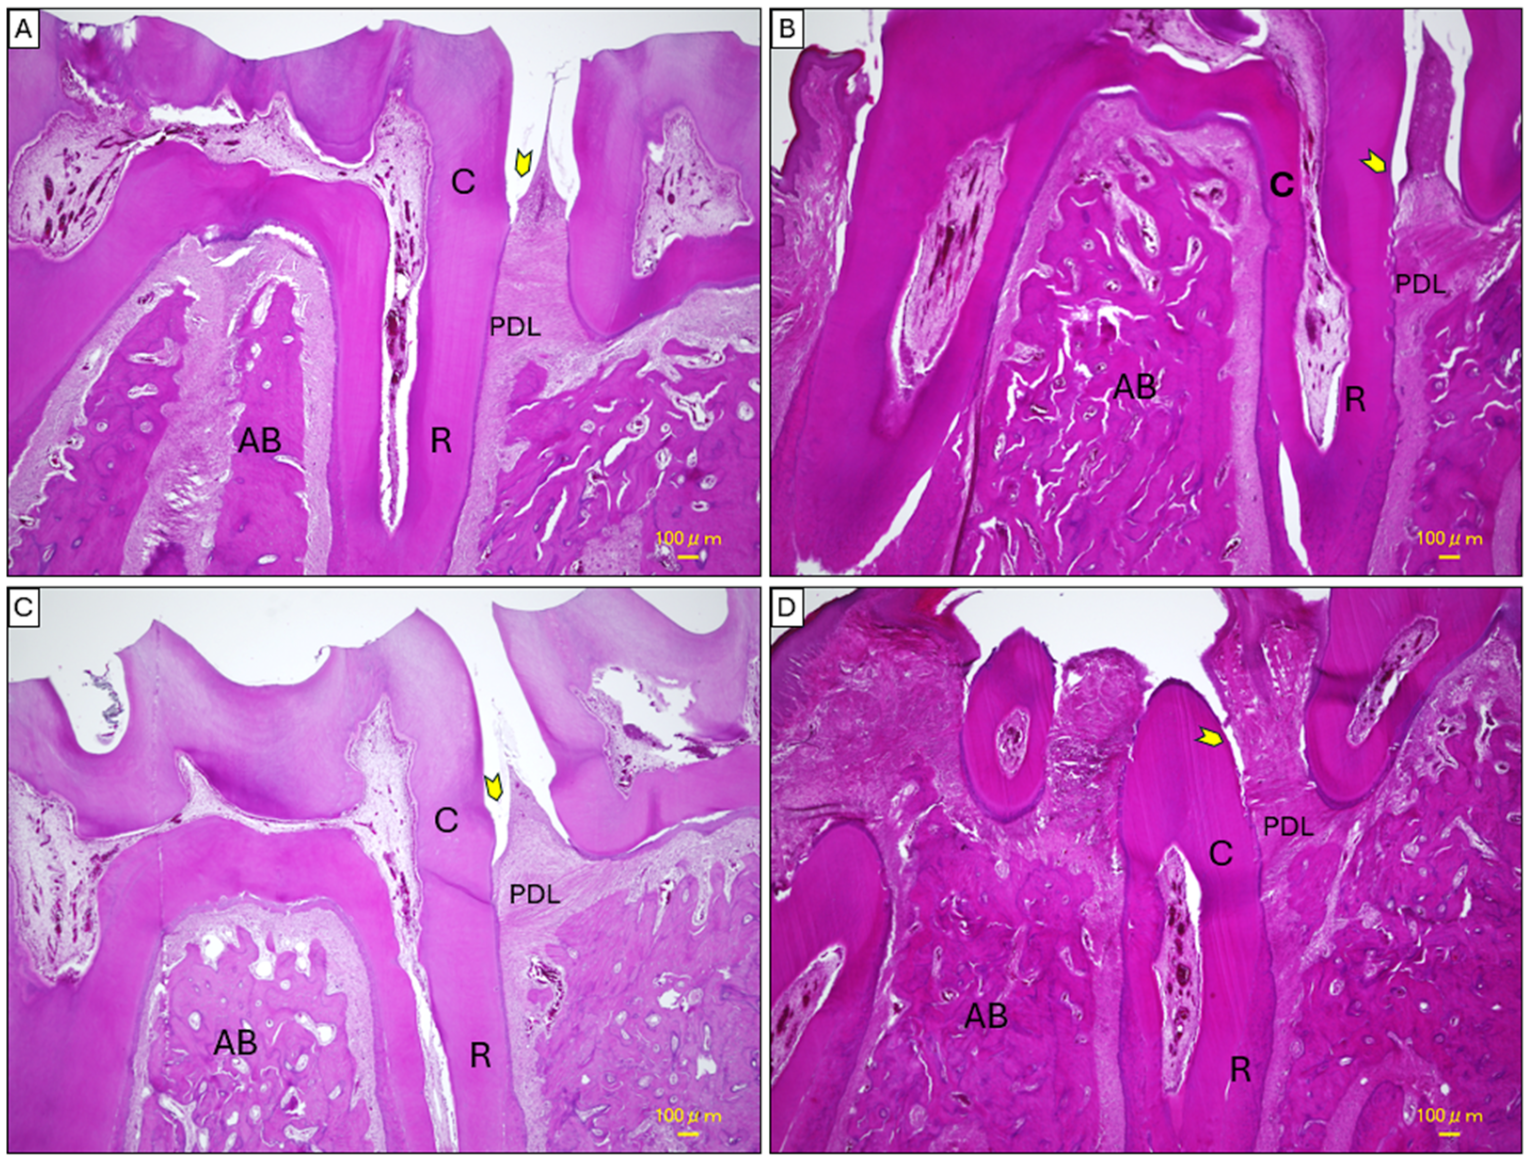

2.4. Histopathological Analysis of Mandibular Tissues

4.8. Histopathological Examination

4.8.1. Mandibular Tissues

4.8.3. Staining Procedures

H&E Staining